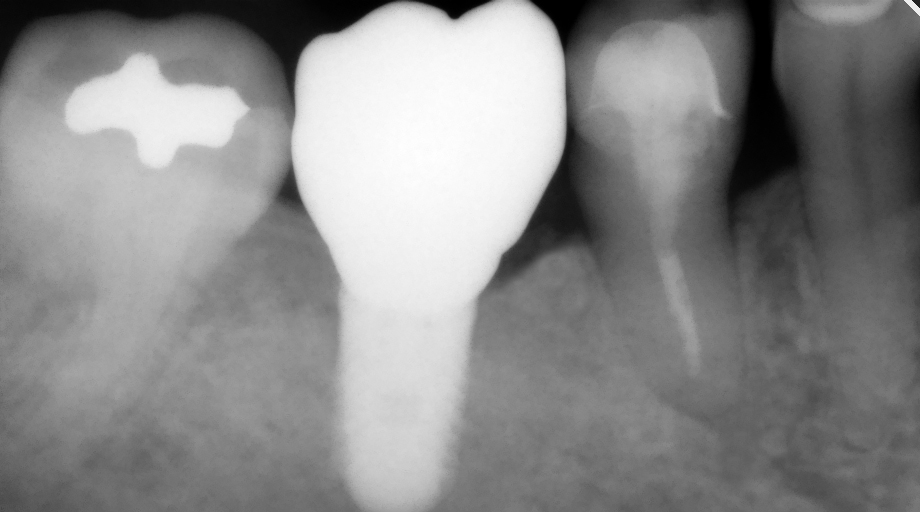

A 4.8 mm x 10 mm implant (Straumann® Bone Level Tapered [BLT], Straumann) had been placed at the mandibular first molar site and was ready for restoration. A custom healing abutment was fabricated and inserted at the time of surgical implant placement and soft tissue was sutured around the abutment using 4/0 Glycolon sutures (Osteogenics Biomedical, osteogenics.com) (Figure 13). A periapical x-ray was taken at the time of placement of the custom healing abutment to confirm full seating (Figure 14).

Fig 13. A custom healing abutment was created to replicate the emergence profile for a mandibular molar, which is square in cross-section.

Figure 13

Fig 14. A periapical radiograph of the custom healing abutment on the implant demonstrated the development of a natural emergence profile for a mandibular molar to replicate the missing natural tooth.

Figure 14